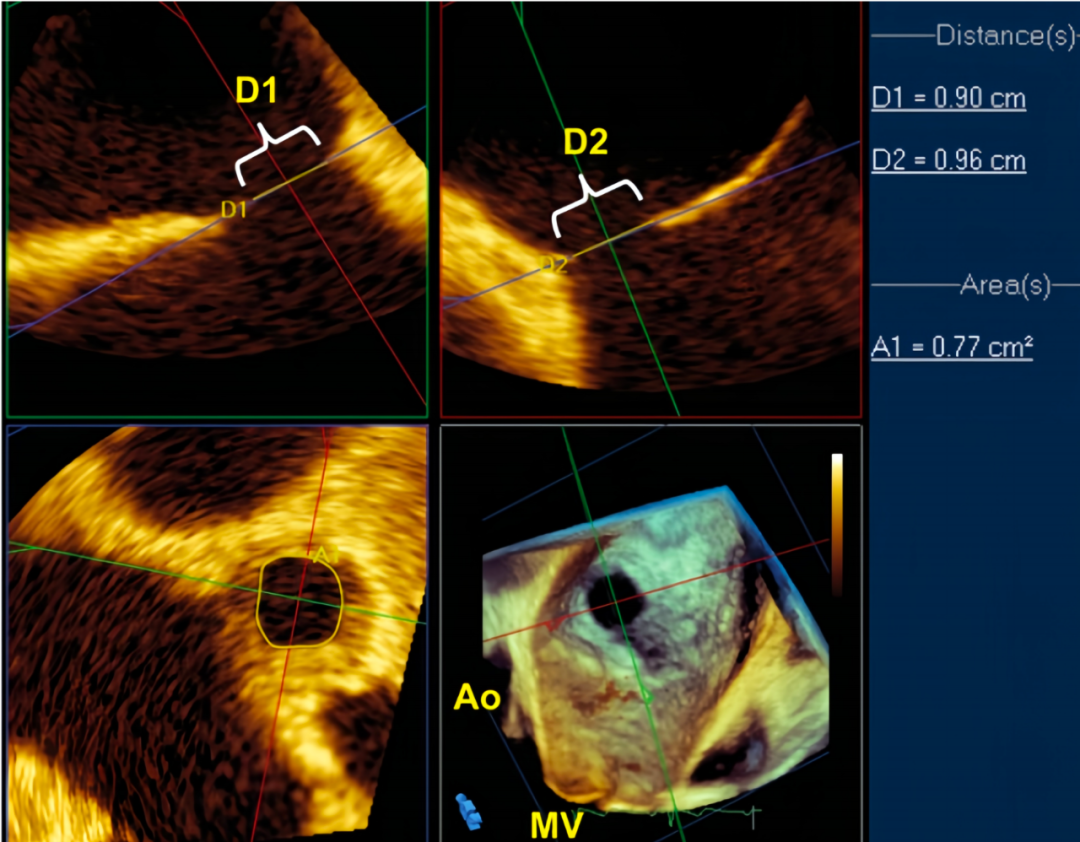

RT 3D TEE可以更好的确定ASD的数目、形态和位置,并可采用左房观或右房观,确定缺损位置与周围组织结构的空间关系,是经胸超声检查的重要补充。RT 3D TEE甚至可以修正既往检查结果,从而影响或改变患者治疗方式。

在上述切面中测量缺损残端大小,有助于确定确定是否能够进行封堵。ASD多数为椭圆形,一定要选择不同切面分别进行测量,尽量显示其内径最大值。

上下径最大的ASD,测量时,可能在双房心切面中才能显示内径最大值

如患者ASD前后径最大,则在主动脉短轴切面中才能显示

在进行TEE检查时,除进行缺损大小定量外,还应该注意测量缺损边缘,距离周围组织的残端大小,这种决定患者是否适合进行封堵的关键。

在对ASD残端评估时,起码应该有六个残端的具体测值

在对ASD残端进行评估时,ASD距二尖瓣环及腔静脉距离起码要>5mm,封堵时才安全。距主动脉侧可无残端,但其对侧残端需>5mm,且必须为硬缘;如一侧为软缘,则计为ASD。